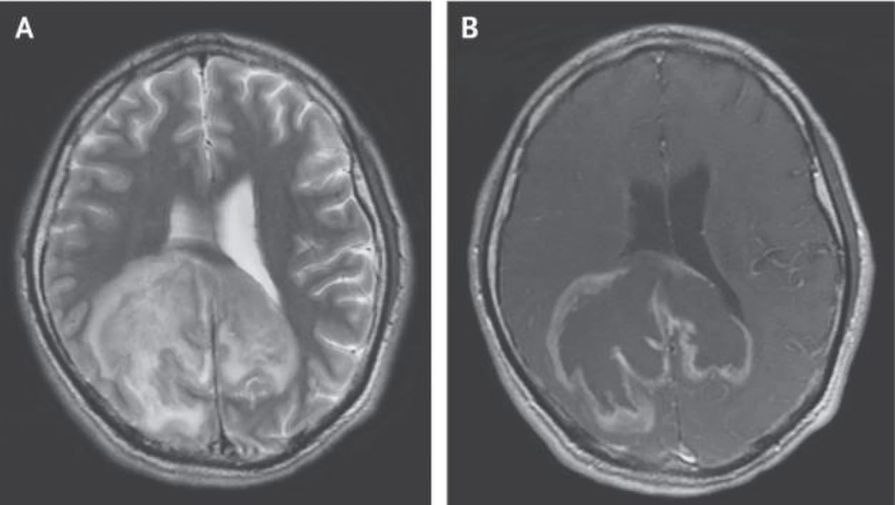

Первоначальным предположением ученых было наличие у девочки синдрома Ретта, который возникает только у женщин, и связан с мутацией в гене MECP2, однако проверки состояния нервной ткани показали, что это не так. В ходе дальнейших исследований, оказалось, что причиной происходящего с девочкой была ранее неизвестная мутация в гене MFSD8, который отвечает за перенос белков и других молекул внутри лизосом.